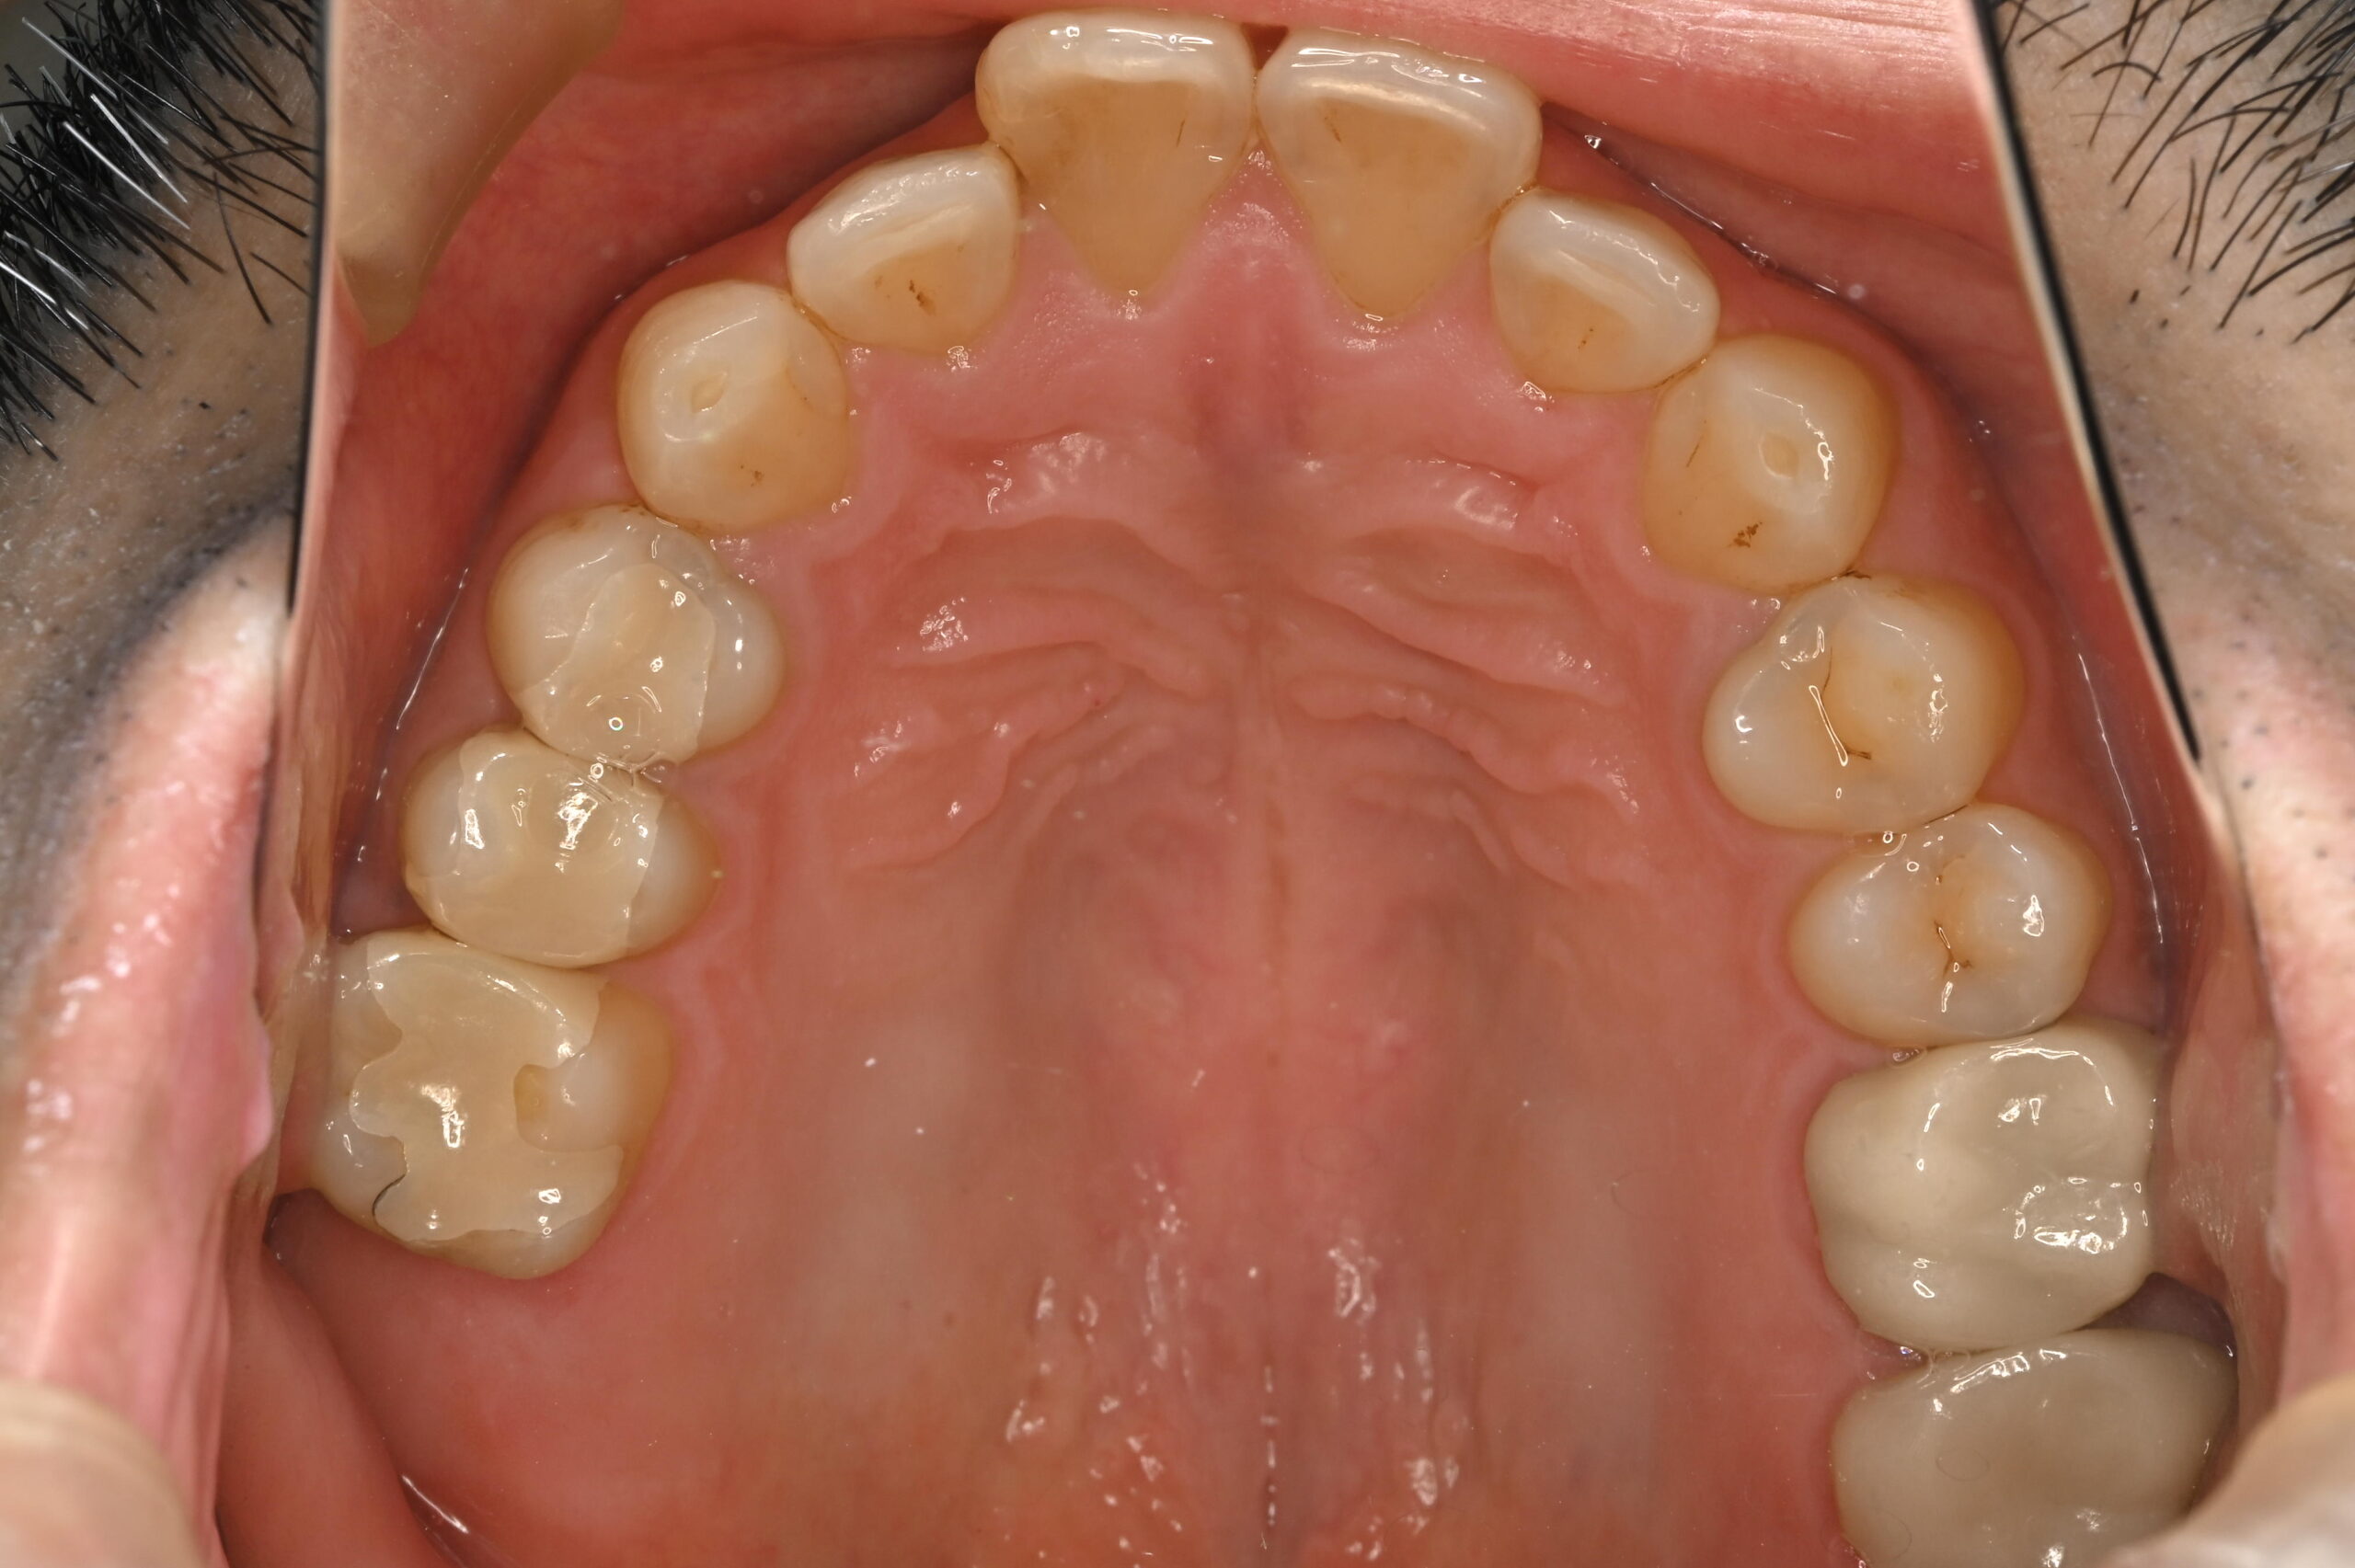

奥歯の銀歯をモノリシックジルコニアで白く改善

年齢・性別

30代/男性

主訴

左上5・6を銀歯を白くしたい

治療方法

咬合状態などから、丈夫なジルコニアで製作

費用

モノリシックジルコニア 77,000円×2本

合計:154,000円

*価格は税込です

メリット

• 補綴装置が白くなるので、口腔内が自然色になる

デメリット・

副作用

• セラミックの丈夫さを上げるため厚く製作する必要があるため、メタルからのやり変えは歯を削る量が多くなる